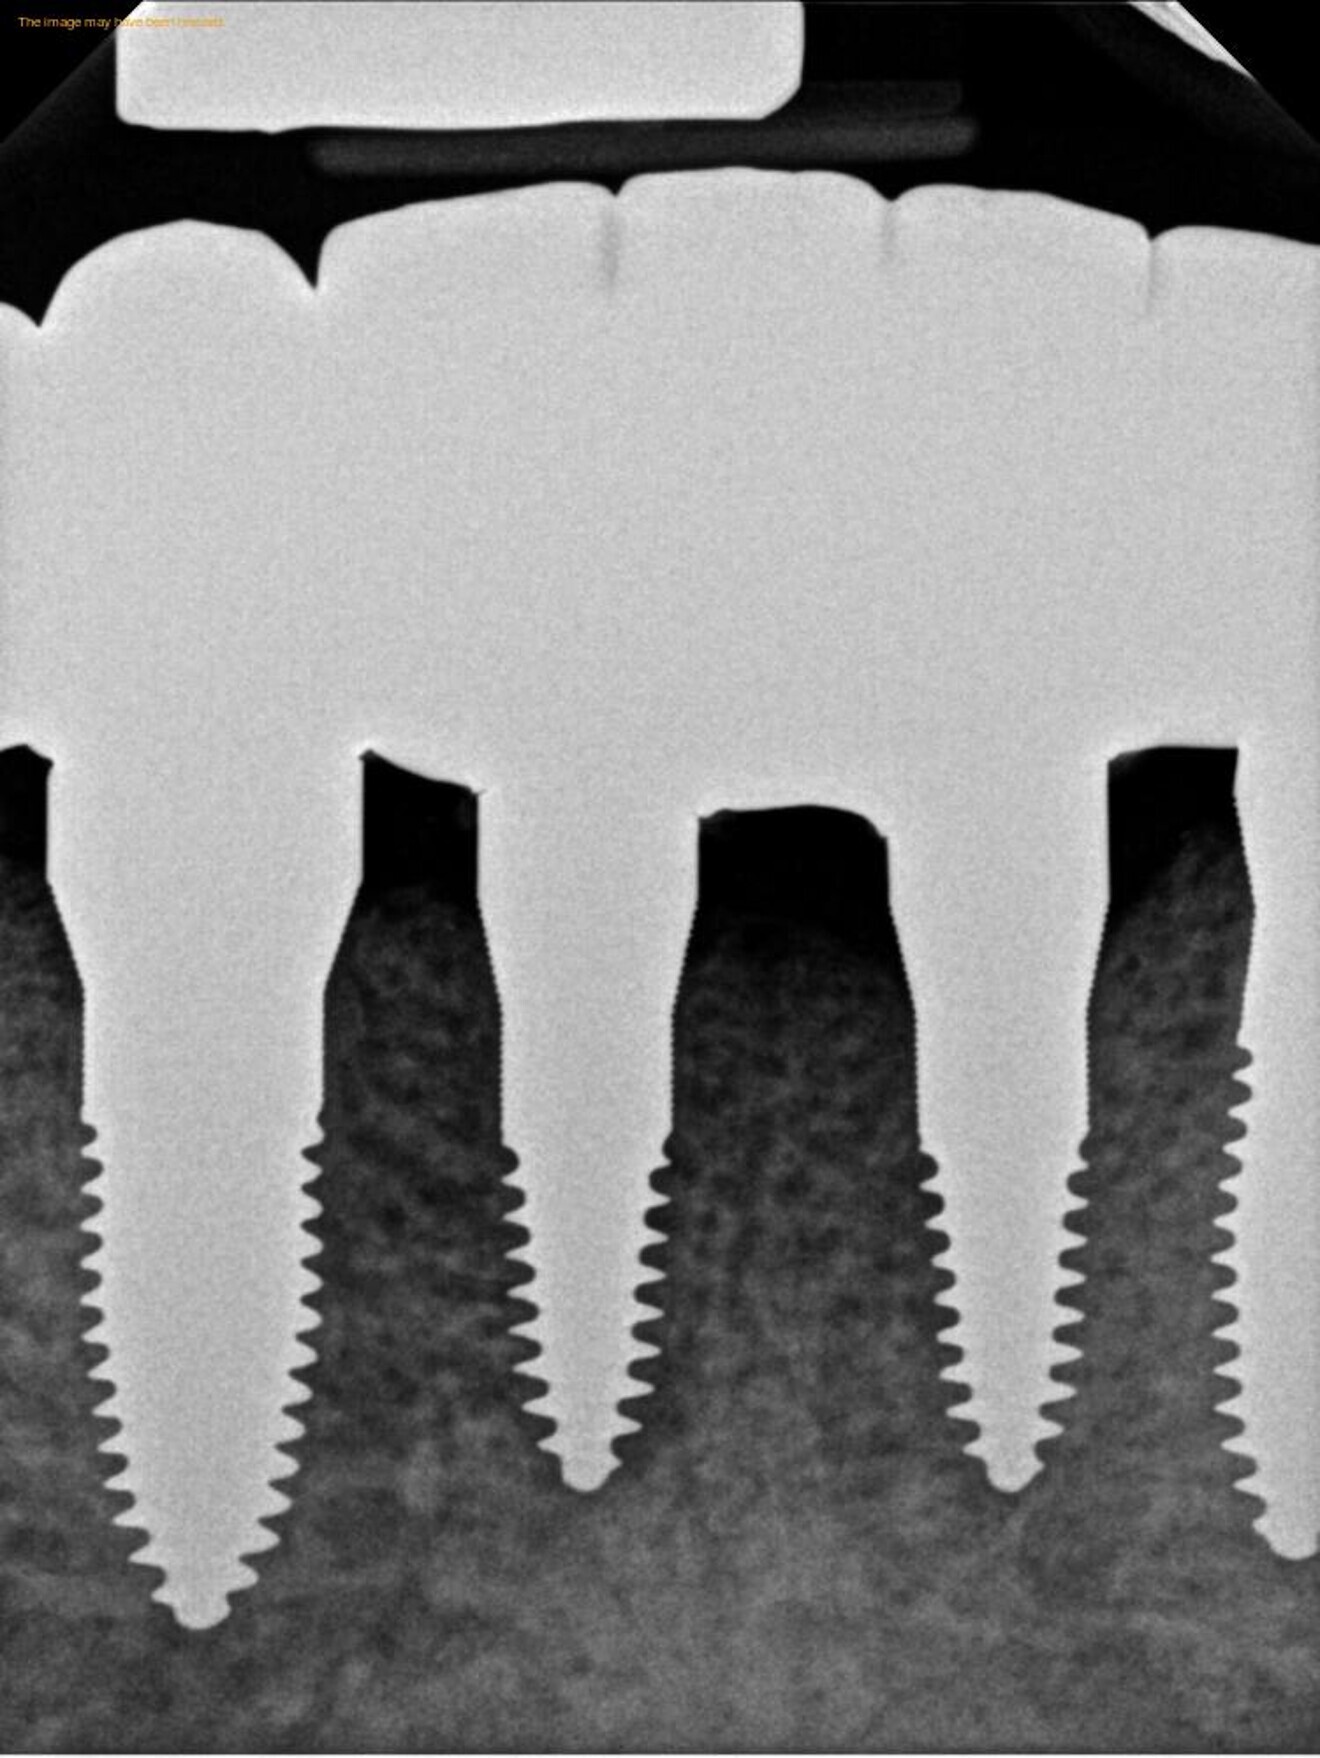

Figs. 17a–c: Final radiographs showing the bone levels and final restoration.

Fig. 17b.

Fig. 17c.

A final full-arch zirconia restoration was manufactured, and the final seating was verified with radiographs (Fig. 17) and cemented with PANAVIA SA Cement Universal (Kuraray Noritake Dental). The patient returned two weeks later for an occlusion check and adjustment along with an oral hygiene check. Pink firm gingiva around all the implants was noted such that it was even difficult to get a probe into the sulcus (Fig. 18).